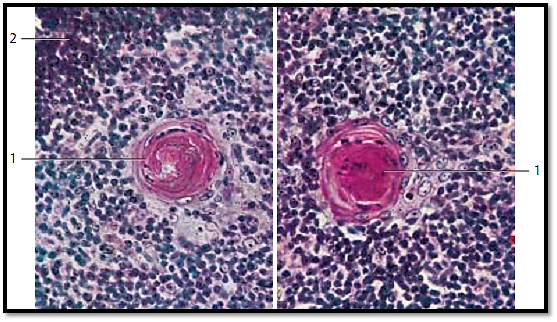

Thymus

Hassall corpuscles 2 are characteristic elements of the thymus medulla. They consist of several concentric layers of reticulum cells in an arrangement reminiscent of an onion. The reticulum cells of ten show hyaline degeneration. Therefore, they occasionally look homogeneous and stain intensely with eosin. Cysts may form as well. A remarkably enlarged epithelial reticulum cell usually occupies the center of the Hassall corpuscle. Medulla cells form a layer around this center. The diameter of Hassall corpuscles is 20–50 0 μm. Their function is unknown. They may arise from ectodermal tissue because analytical data show prekeratin and keratin in their cells, similar to the cells of the epidermis. Several epithelial thymus cells biosynthesize substances, which presumably have hormone character. Known, well-defined substances are thymosin , thymopoietin and thymulin , among others.

1 Hassall corpuscle

2 Cortex

Stain: alum hematoxylin-eosin; magnification: × 240